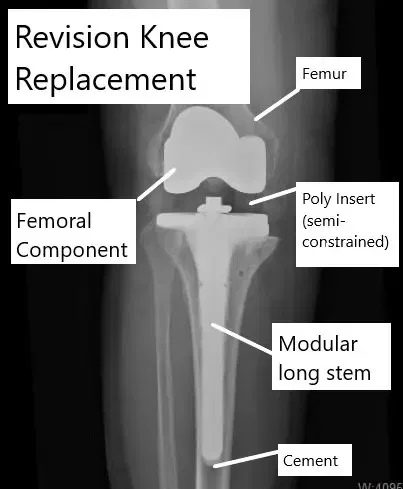

El reemplazo articulado de rodilla se utiliza cuando el tejido blando o el hueso no pueden estabilizar un implante estándar. La prótesis tiene un mecanismo de bisagra o giratorio que conecta los componentes femoral y tibial. Los implantes articulados pueden utilizarse en cirugía de revisión, deformidades graves, tumores, infecciones, fracturas o laxitud mayor de ligamentos.

Reemplazo de rodilla articulada

Los implantes utilizados en una prótesis total de rodilla tienen formas y tamaños diferentes. La elección del implante utilizado en una prótesis total de rodilla depende de la cantidad de hueso, la calidad del hueso, el tejido blando que rodea la rodilla, cualquier intervención quirúrgica previa y también del historial médico del paciente. Un reemplazo de rodilla articulado es un reemplazo complejo que requiere un implante especial con bisagra o plataforma giratoria.

Durante una cirugía de reemplazo de rodilla, el cirujano extirpó los extremos enfermos del extremo inferior del fémur y la parte superior de la espinilla. La sustitución protésica de las partes extraídas recrea la articulación natural de la rodilla sin ninguna enfermedad.

Las partes protésicas están hechas de metal y plástico de alta calidad. El componente femoral y el tibial están hechos de metal, mientras que el inserto o separador está hecho de plástico de alta calidad. El separador de plástico ayuda a deslizarse suavemente de las superficies metálicas opuestas.

Revisión de reemplazo de rodilla que muestra el uso de componentes semi-restringidos.

La limitación es la capacidad del implante para proporcionar estabilidad en movimientos hacia adelante hacia atrás y lateralmente. Los implantes restringidos son necesarios ante la pérdida ósea o el trabajo en los ligamentos. Los implantes pueden ser no restringidos, semi-restringidos o completamente restringidos dependiendo del grado de estabilidad que proporcionen.

Los implantes restringidos vienen en diferentes diseños. El implante con bisagra restringido que se usaba originalmente ha sido en gran medida reemplazado por un implante con constrención giratoria. En un implante de reemplazo de rodilla articulado, hay una varilla entre los componentes femoral y tibial.

La biela tiene un mecanismo de bisagra para evitar la sobreextensión de la junta. Este diseño solo permite moverse hacia adelante y hacia atrás y evita cualquier movimiento lateral o giratorio.

La pérdida de movimiento lateral y de rotación ejerce una tensión adicional en la interfaz hueso-implante y puede provocar el aflojamiento del implante o la fractura periprotésica. El implante con restricción giratoria también permite el movimiento de rotación alrededor de la bisagra protésica. La bisagra se encuentra cerca del componente femoral y una plataforma giratoria está unida a la placa tibial.

La acción rotatoria ayuda a distribuir las tensiones de forma más uniforme durante el movimiento, manteniendo la estabilidad ante la pérdida ósea o la laxitud de los ligamentos. Los implantes articulados se utilizan principalmente en cirugías de revisión y en cirugías primarias complejas de reemplazo de rodilla que implican deformidades graves o tumores, o cirugías de salvamento, etc.

Los implantes de reemplazo de rodilla articulados también son modulares y permiten la adición de cuñas o triángulos metálicos para compensar la pérdida ósea. La modularidad del vástago también permite añadir vástagos largos para proporcionar estabilidad.